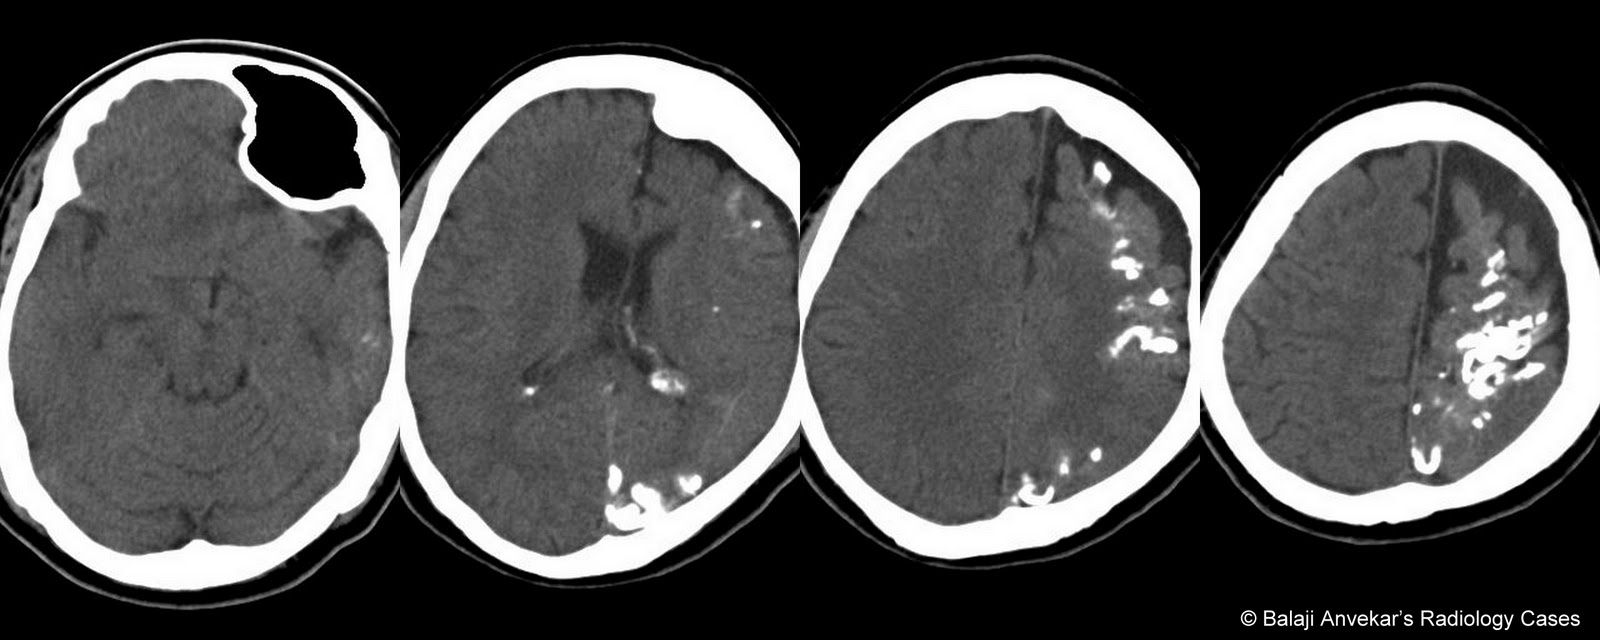

Sturge weber syndrome radiology. Sturge weber syndrome or encephalotrigeminal angiomatosis is a phakomatosis characterized by facial port wine stains and pial angiomas. It is part of a wide. Radiology articles covering imaging techniques findings symptoms diagnosis staging treatment prognosis and follow up. Peer reviewed and up to date.